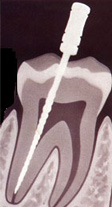

1. Удаляется воспаленная ткань пульпы («нерв»). В таком состоянии она представляет опасность как место размножения болезнетворных бактерий. 2. В корневой канал плотно вводится пломбирующий материал, который герметично закрывает канал.

Доступ к пульповой камере врач-стоматолог получает, удалив ткани дентина, пораженные кариесом. Далее, специальными инструментами для обработки каналов, происходит очистка корневого канала от пораженной ткани пульпы. Дезинфицирующими растворами обрабатываются стенки канала для удаления оставшихся микробов и предотвращения дальнейшего роста инфекции. На протяжении всего процесса лечения проводятся рентгенологическая диагностика хода лечения и состояния канала до и после лечения. Высушив канал от растворов, доктор проводит заполнение канала пломбировочным материалом – гуттаперчевыми штифтами, которые при нагревании заполняют все полости и микропоры.